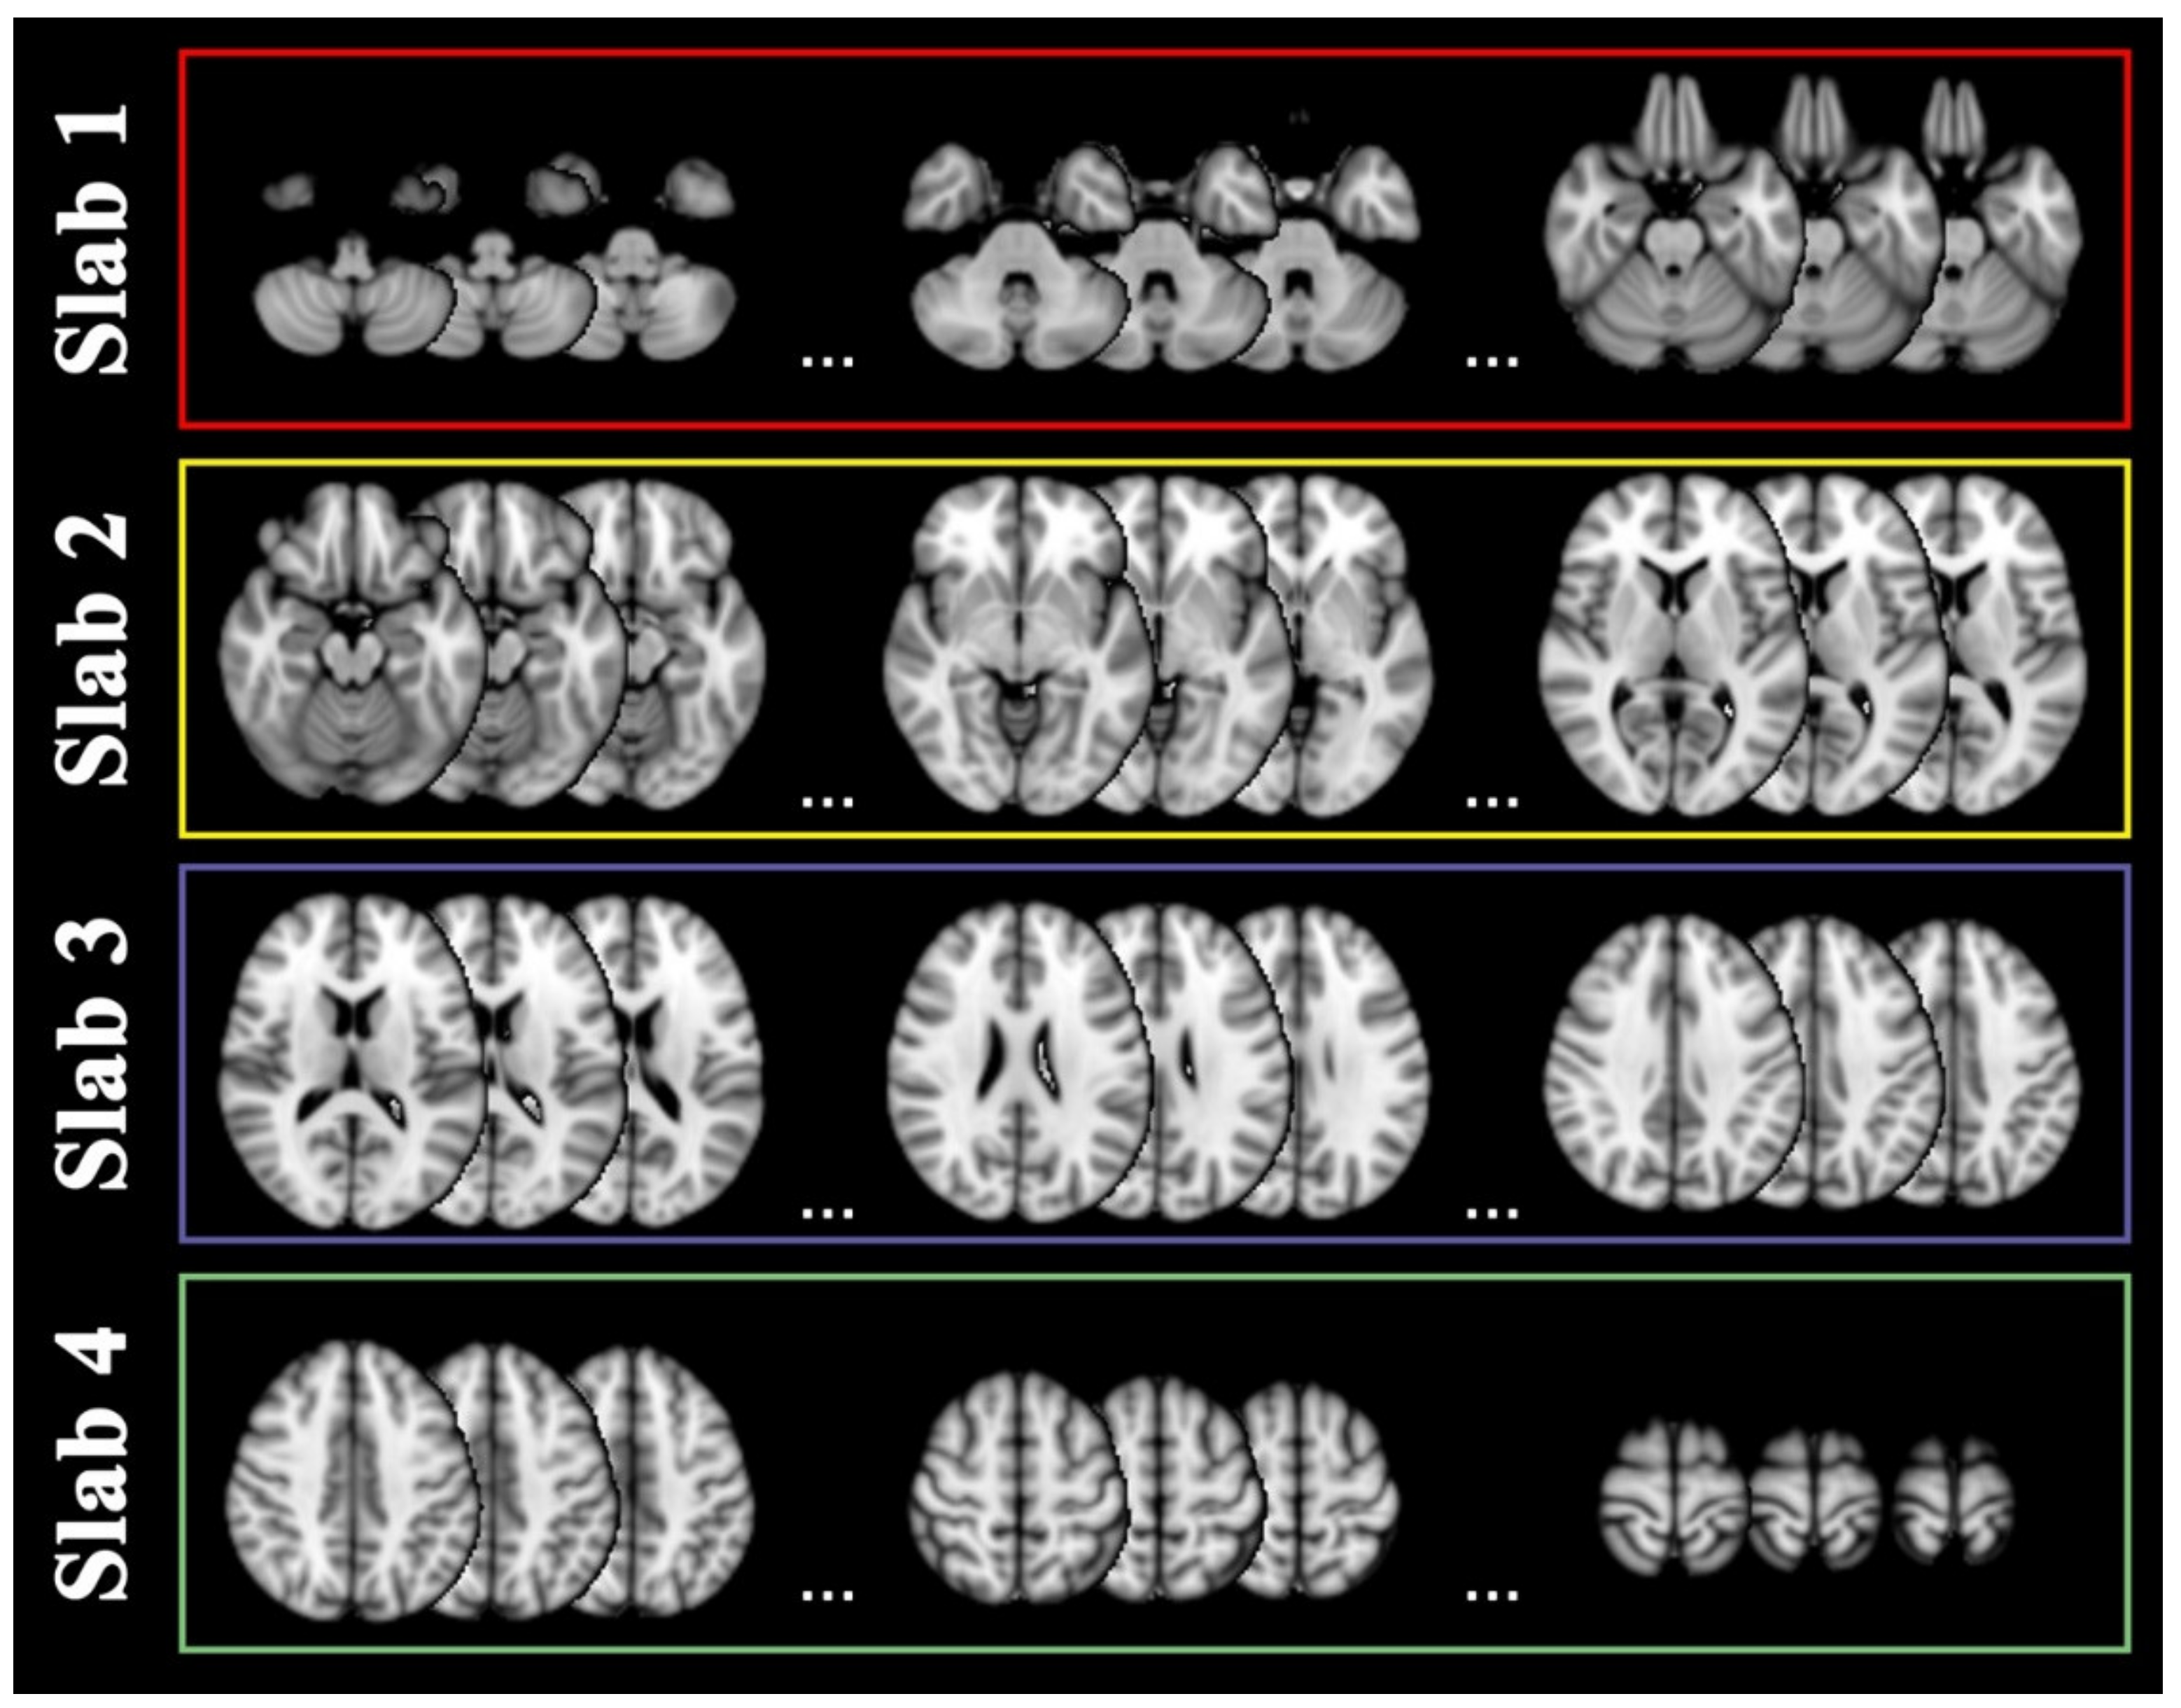

4.4. Slab Selection